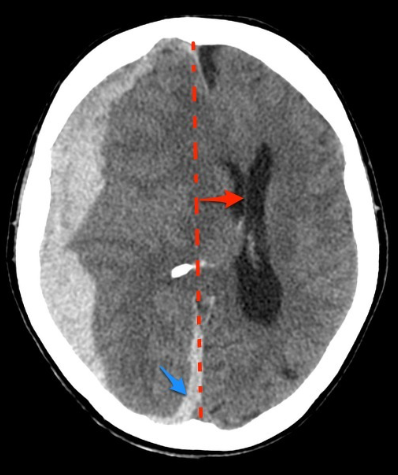

What does midline shift look like on CT head, and what conditions does it indicate?

A

CT finding: Brian tissue displaced across midline so structures look wavy

Indicates increased intracranial pressure secondary to traumatic brain injury, stroke, tumour, haematoma